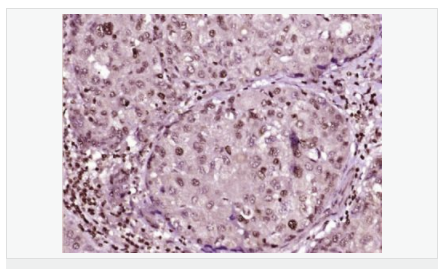

交叉反應(yīng):Human,Mouse,Rat(predicted:Dog,Pig,Rabbit,GuineaPig) 推薦應(yīng)用:IHC-P,IHC-F,ICC,IF,Flow-Cyt,ELISA

| 產(chǎn)品應(yīng)用 | ELISA=1:5000-10000 IHC-P=1:100-500 IHC-F=1:100-500 Flow-Cyt=1μg/Test ICC=1:100 IF=1:100-500 (石蠟切片需做抗原修復(fù)) not yet tested in other applications. optimal dilutions/concentrations should be determined by the end user.  |